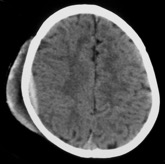

il est affirmé sur le scanner

qui montre une collection hyperdense (avec souvent une composante hypoderme) à la face interne de la voûte : typiquement en lentille biconvexe, souvent en fait en forme de lentille concave en dedans. il est alors souvent pris pour un hématome sous-dural : on les distingue par le fait que ce denier ne s’accompagne en général pas de signes d’impact homolatéraux (hématome sous-cutané, fracture).